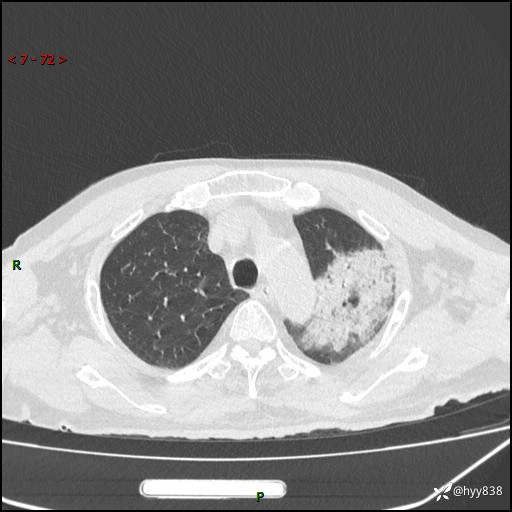

胸部CT复查(2024.8.5)